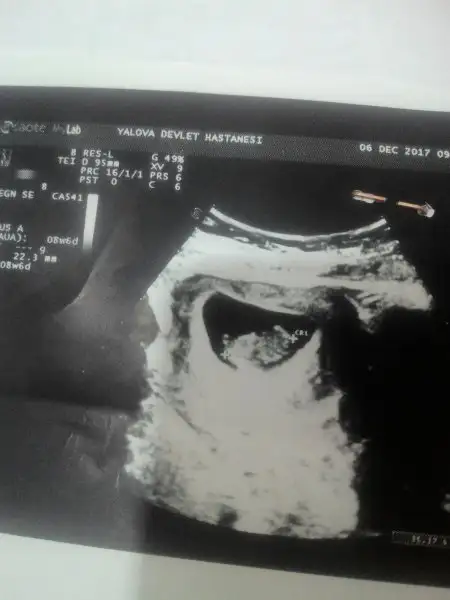

asagidakide 8.6

1515098677554-328991367.webp